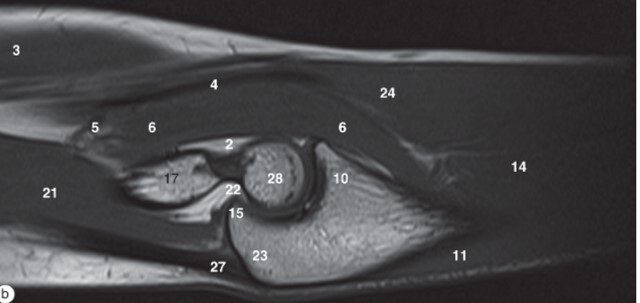

Q

Label 1,4,6,16,32,33

A

1-Lt. Basilic vein

4=-Lt. Brachialis muscle

6-Capitulum of Lt. humerus

16=Head of Lt. radius

32-Trochlea of lt. humerus

33= Tuberosity of lt. radius

Label 6,16,17,18,22,25,32

6=Capitulum of lt. humerus

17=Lt. Humerus

18=Lateral condyle (lt. humerus)

22=Medial condyle (rt. humerus)

25=Olecranon fossa of lt. humerus

32=Trochlea of lt. humerus

Label 19 and 26

19-Lt. Triceps brachii muscle

26-Olecranon process of lt. ulna

Label 3,6,8,8,16,17,19,25

3=Biceps brachii muscle

6=Brachialis muscle

8=Capitulum of humerus

9=Cephalic vein

16=Radial head

17=Humerus

19=Triceps brachii

25=Radius

Label 3,6,9,17,21,23,28

6-Brachialis muscle

9=Coronoid process

21=Triceps brachii

23=Olecranon process of ulna

28-Trochlea of humerus